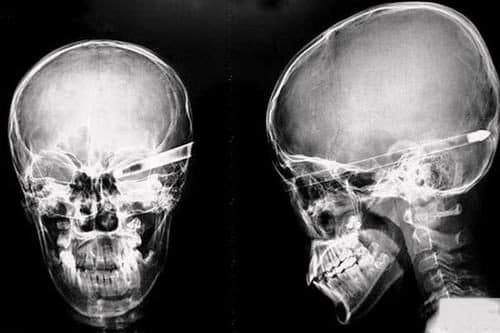

Chụp X quang sọ não

Khi gặp phải các vấn đề ở sọ não như chấn thương, dị tật, viêm các xoang…, người bệnh thường được chỉ định chụp X quang sọ não để chẩn đoán. Tuy nhiên, đây là cơ quan khá phức tạp và khó quan sát hơn qua phim chụp, cần được thực hiện và đọc phim […]